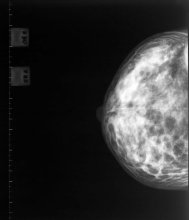

A new study has revealed the benefits of mammograms for women aged 75 years and older.

The research, published in the journal Radiology, shows that mammogram-detected breast cancers are found at an earlier stage; require less treatment; and lead to better survival rates.

Renewed questions have been raised about the value of mammograms after a Canadian study suggested that it does not reduce the number of deaths from breast cancer.

BCAC chair Libby Burgess says while the latest research is thought-provoking, it should in no way prompt New Zealand women to stop getting their free mammograms every two years through BreastScreen Aotearoa.